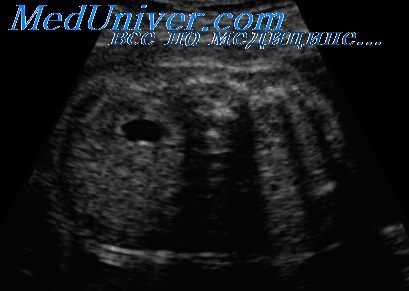

Если при ультразвуковом обследовании в почечных лоханках визуализируется жидкость, важно определить, является ли это признаком гидронефроза или просто небольшим количеством жидкости, которое часто наблюдается в почечных лоханках плода при физиологическом течении беременности во втором или третьем триместре. Диагноз гидронефроза устанавливается в тех случаях, когда обнаруживается расширение почечных чашечек или если переднезадний диаметр почечной лоханки, измеренный при поперечном сечении брюшной полости на уровне почек, достигает 8 мм в 16-20 нед беременности или 10 мм после 20 нед.

Чтобы не пропустить формирующийся гидронефроз почки, выявление переднезаднего диаметра почечных лоханок на уровне 4-7 мм в 16-20 нед и 5-9 мм после 20 нед беременности следует расценивать как подозрительное в отношении вероятности его развития и проводить повторные обследования в динамике для исключения или подтверждения этого состояния. Эти критерии основаны на результатах исследований, показавших, что постнатальный прогноз зависит от диаметра почечных лоханок и наличия расширения почечных чашечек, обнаруживаемых в пренатальном периоде.